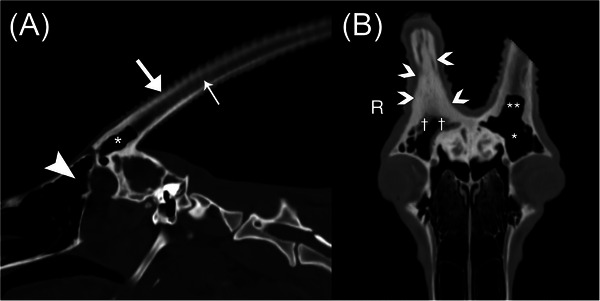

A 3-year-old male Scimitar-horned oryx presented for evaluation of an acutely deformed right horn with right head tilt and right facial pain. Computed tomographic evaluation revealed an increased volume of central fluid/soft tissue attenuation with gas-attenuating foci within the right horn. The right horn was amputated at the right horn base. Imaging and histopathologic features were consistent with emphysematous osteomyelitis. Following treatment, the patient returned to normal behavior. This is the first veterinary report describing the computed tomographic features of a horn infection in a Scimitar-horned oryx.